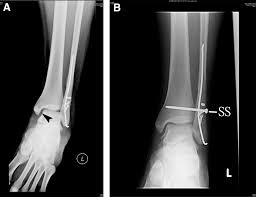

Syndesmosis

All about the Syndesmosis Ligament and Syndesmosis Injuries The syndesmosis ligament in the ankle supports you every time you stand…